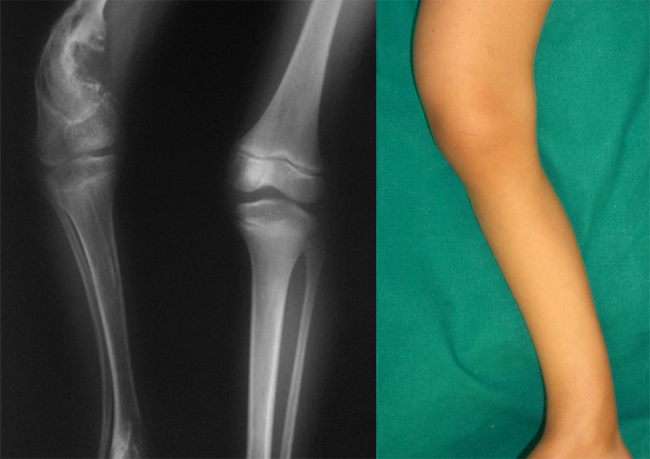

Deformità femoralePaziente di 6 anni. Deformità femorale distale in varismo e tibiale distale in valgismo. Ipometria dell’arto inferiore sinistro di 10 cm. Diagnosi e trattamento?